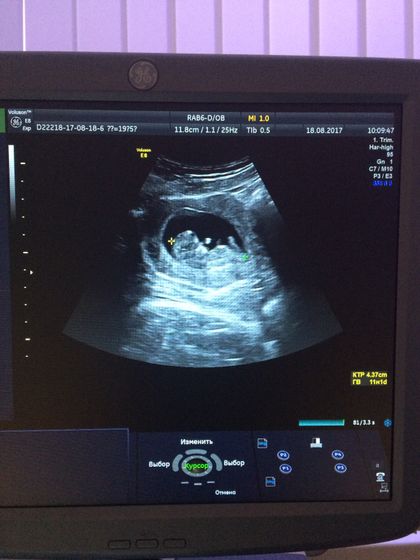

Направили меня на первый скрининг, сегодня ходила)

Итог: отправили меня домой до 29 августа? срок по узи всего 11 недель и 1 день)

Но за то, я успокоилась, увидела своего малыша ?

Спрашиваю ещё у неё «можно сделать фото?», а она мне так отвечает «там ещё нечего фотографировать, но если тебе так надо, то сфотографируй» ?

какой хорошенький ребятёнок???

Даа, видела его бусинкой ? а сейчас такой большой☺️

Мне на первом скрининге сказали пол. Так что все там видно)

Хамка врач. Как же это нечего?! Все уже есть: головка, ручки, ножки)) уже человечек малюсенький